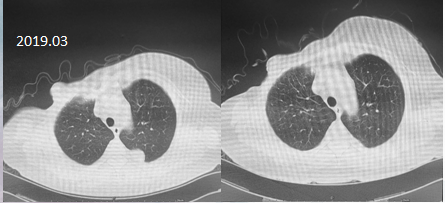

2018.11-2019.03二线治疗采用多西他赛+卡培他滨,判效SD

胸部CT: